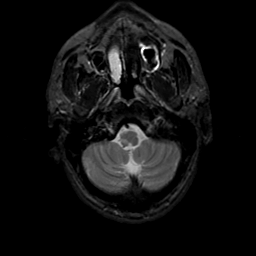

MR Study #22, December 1, 1991 -- Slice #6